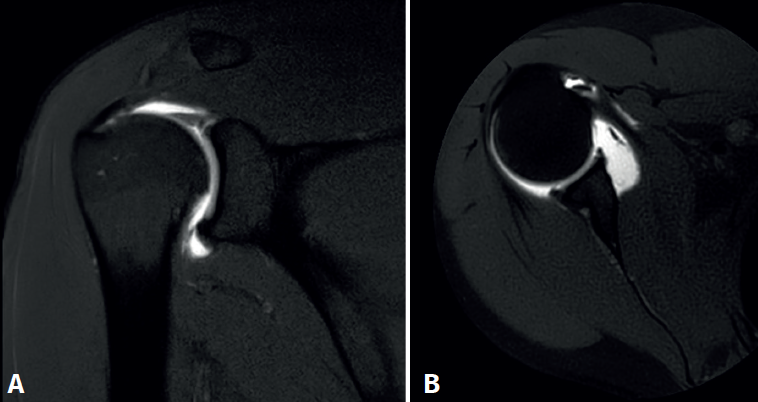

El artículo de revisión, escrito por Robert D. Boutin en 2018 y titulado “MR imaging of SLAP lesions”(10), nos proporciona criterios diagnósticos detallados para identificar las lesiones de SLAP mediante RM o artro-RM. Este trabajo se convierte en una referencia clave para profesionales médicos, permitiéndonos adquirir un mejor entendimiento de esta técnica diagnóstica y sus utilidades.

Además, destaca la importancia del conocimiento específico necesario para interpretar las imágenes de la RM, incluyendo la comprensión de la apariencia normal del labrum, sus variaciones anatómicas y los patrones característicos de las lesiones de SLAP (Figura 3).

Dentro de los criterios diagnósticos descritos en el artículo, se encuentra la visualización de la línea simple o ramificada de alta intensidad de señal en el labrum superior, el desprendimiento con alta intensidad de señal entre el labrum y la cavidad glenoidea, y el quiste paralabral que se extiende desde el labrum superior.

Esta comprensión no solo facilita la identificación precisa de las lesiones, mejorando las directrices diagnósticas en la práctica clínica, sino que también permite clasificar los diversos tipos de SLAP presentes en los pacientes, lo cual optimiza la planificación preoperatoria. Aunque hay que señalar que la correlación radiológica y clínica de estos hallazgos es limitada, ya que se puede diagnosticar un SLAP mediante un estudio radiológico en un paciente sin esta clínica.